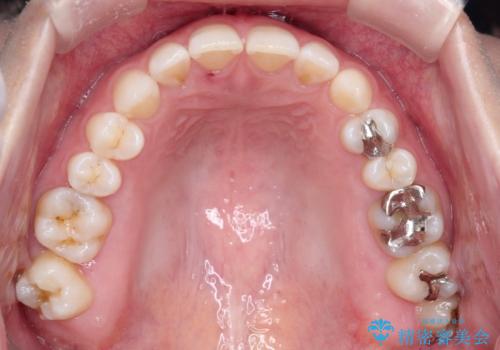

- 前歯の正中離開(すきっ歯)の改善を希望され来院された患者様です。

初診時の歯並びの状態としては、上顎中切歯間に1mm程の隙間があり、その他に見た目に関して気になるような問題点はない状態でした。

インビザライン(マウスピース)にて上顎のみの矯正治療を行いました。